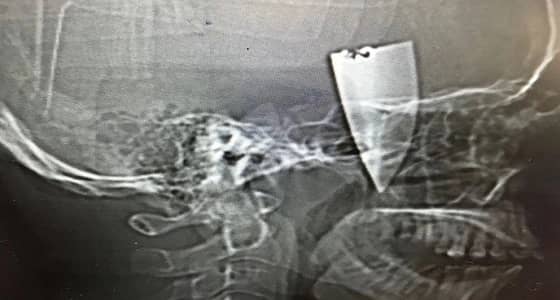

نجح بفضل الله فريق جراحي بمجمع الملك فيصل الطبي بمحافظة الطائف في إستخراج نصف سكين حادة من وجه شاب عشريني. بعد أن وصل في حالة طارئة إلى قسم الطوارئ ، حيث تم الكشف عليه واتضح انه مصاب بجرح قطعي في الجهة اليمنى من فروة الرأس بطول 10سم,وتم على الفور إجراء الاسعافات الاولية ، وبإجراء فحوصات إشعاعية إتضح وجود جسم غريب داخل مدفون بالأنسجة ، وممتد من فروة الرأس حتى اسفل القوس الوجيني الايمن مع إنعدام الحركة من الفك السفلي وأدخل الشاب إلى غرفة العمليات ، وقام فريق جراحي مكون من أطباء جراحة ووجه وفكين بالعمل على إستخراج الجسم الغريب الذي إتضح أنه عبارة قطعة نصف سكين طولها 7سم..وتمت العملية دون أي مضاعفات تؤثر على صحة الشاب.